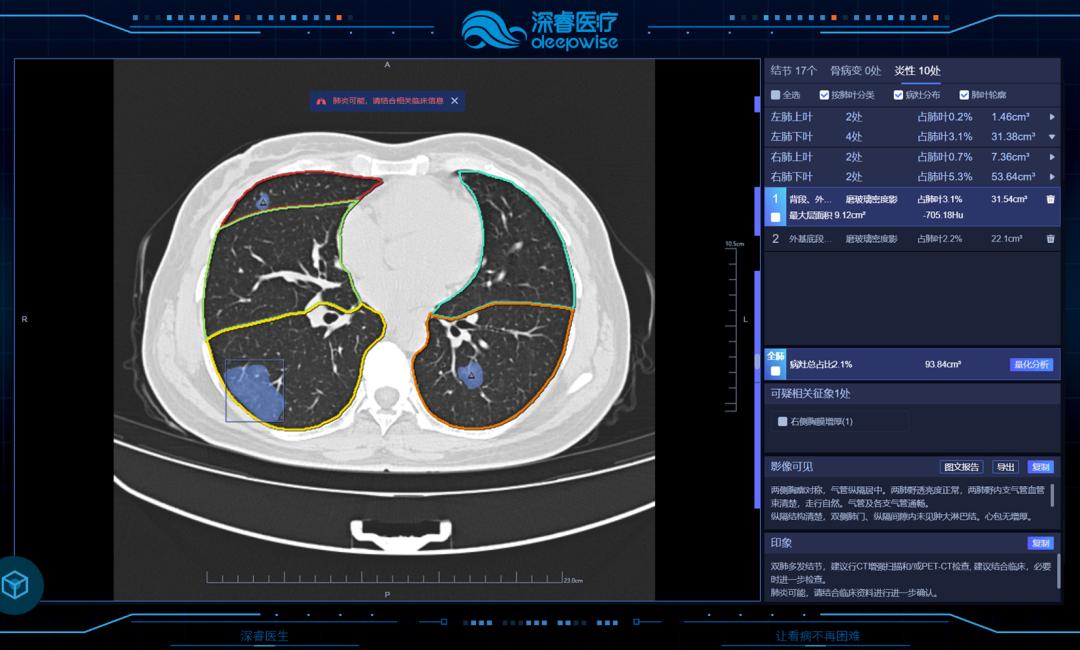

此外,人工智能在肺部病变的临床诊断的应用已落地且越来越成熟。

在中国临床AI肺结节诊断系统有三家公司获批:深睿医疗、推想科技、联影智能。